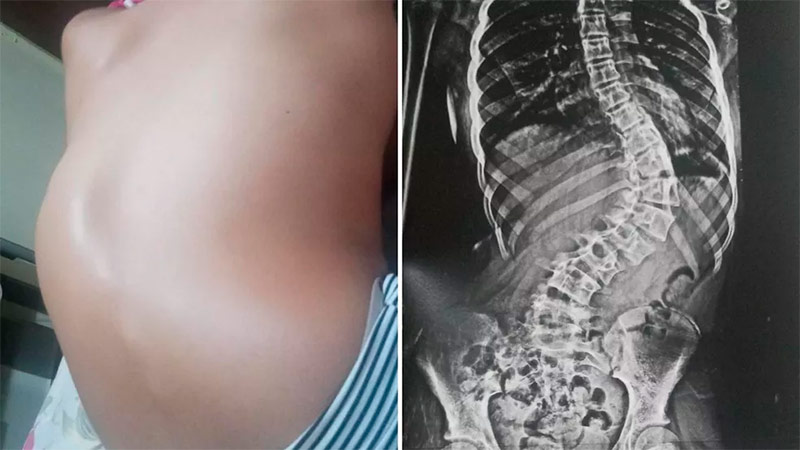

A curvatura na coluna de Agatha Rebeca Mestrello, de 12 anos, já ultrapassou os 100 graus após cinco meses desde a primeira consulta médica, segundo a mãe, Ana Patrícia Maestrello. A moradora de Marília (SP), então, começou a vender bolos para arrecadar o valor estipulado para pagar a cirurgia corretiva.